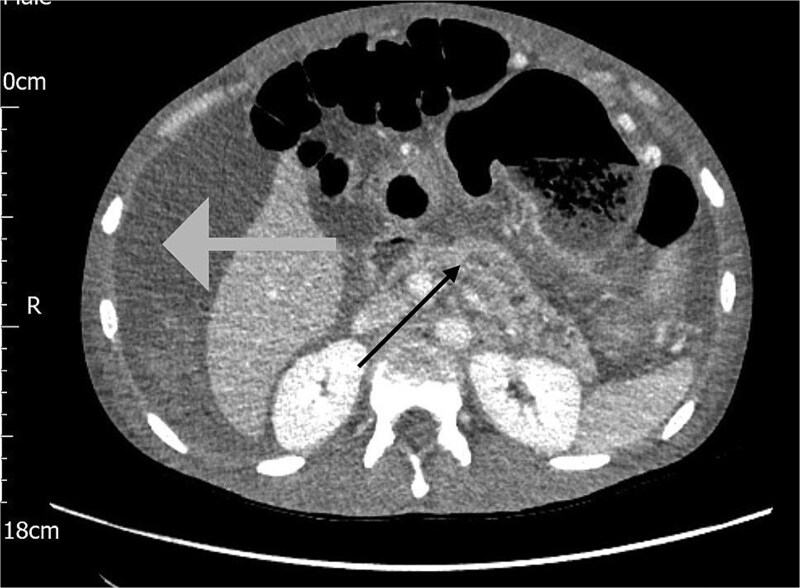

Acute necrotising pancreatitis can lead to severe vascular complications, including venous thrombosis, pseudoaneurysm, and haemorrhage. Acute haemorrhagic pancreatitis, though rare, is life-threatening. Contrast-enhanced computed tomography (CT) scan is the preferred diagnostic tool, with image-guided embolisation as the primary treatment for bleeding vessels. Surgery may be necessary when radiological methods fail. A 39-year-old male with recurrent abdominal pain, distension, and weight loss was initially misdiagnosed with intra-abdominal malignancy based on CT findings of omental deposits. Elevated amylase levels and haemorrhagic ascetic fluid prompted further investigations. A rapid haemoglobin drop and clinical deterioration led to diagnostic laparoscopy, confirming acute haemorrhagic pancreatitis. This case highlights the diagnostic challenges of this condition, which may present subtly and evade standard imaging, resulting in delayed treatment. Clinicians should suspect haemorrhagic pancreatitis in patients with acute abdominal pain, elevated amylase or lipase, and ascites. Early recognition and intervention are crucial for better outcomes.